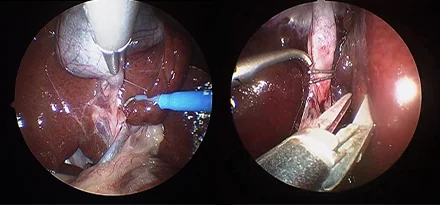

흉강경

복강경과 유사하게 최소 절개를 통해 흉강 수술을 진행하게 됩니다.

작은 구멍으로 카메라 포트가 진입하여 수술 부위를 시각화하고 진단과 치료를 진행할 수 있습니다.

흉강에서는 탐색과 조직생검을 통해 확실한 진단에 도움이 됩니다.

심낭수 치료를 위해 심낭막절제술, 최소침습 폐엽절제, 유미흉의 치료를 위한 흉관결찰(Thoracic duct ligation) 등이 진행될 수 있습니다.

흉강경심막절제술 (Preicardiectomy)

흉강경흉관결찰 (Thoracic duct ligation)

* 리본동물의료센터 케이스 사진으로 무단 복제 및 도용을 금지합니다.